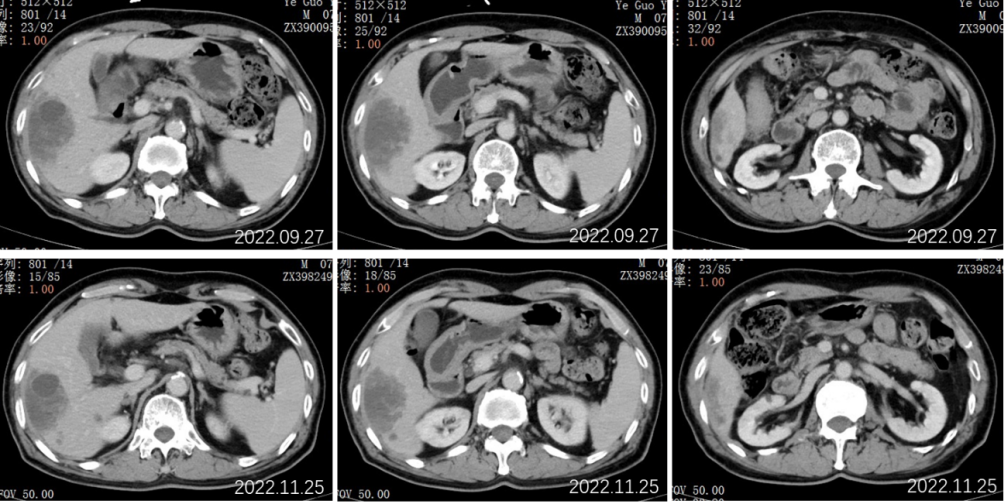

2022.09.27腹部CT增强:肝胆管细胞癌治疗后复查:1、肝右叶多发占位,较前大小相仿,目前仍可见活性;2、肝内及双肾多发小囊肿,相仿;肝S2段小血管瘤考虑,相仿;3、慢性胆囊炎改变;4、肝内钙化灶;前列腺钙化灶。

2022.11.25腹部CT增强:肝胆管细胞癌治疗后复查:对比2022-09-27日:1、肝右叶多发占位,较前大小相仿,目前仍可见活性;2、肝内及双肾多发小囊肿,相仿;肝S2段小血管瘤考虑,相仿;3、慢性胆囊炎改变;4、肝内钙化灶;前列腺钙化灶。